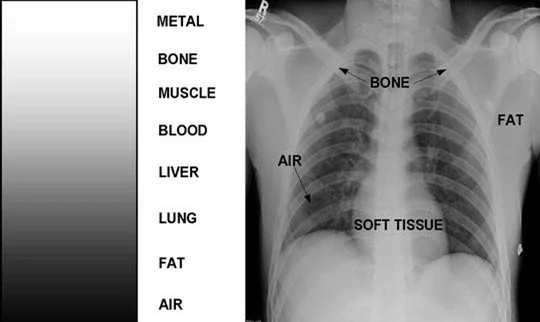

It all stems back to the leak in my lung. As air escapes the lung and moves into the chest cavity surrounding the lung , it seeps out of the chest cavity and moves between the tissues finding the path of least resistance. In the hospital they told me it was subcutaneous air (air under the skin). It filled up my superficial chest and the side of my neck to the point where it seemed I had no neck at all. It was fascinating seeing x-rays that included the subcutaneous air. There were a little gaps;riffs between muscles and skin ,pried apart by the air. When you touched the area you would feel and hear a slight popping. it is not unlike breaking packing bubbles but more subtle. When l hugged someone and our cheeks met, they could hear the popping.